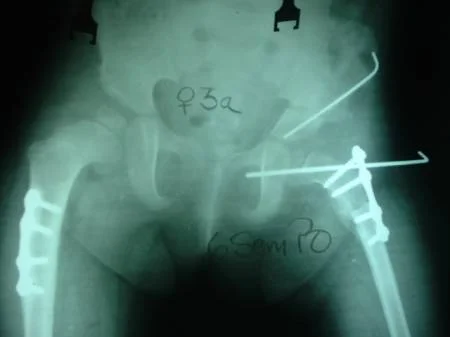

CASO CLINICO: DISPLASIA EVOLUTIVA DE AMBAS CADERAS (LUXADAS)

Paciente femenino de 8 meses de edad, portadora de displasia del desarrollo de ambas caderas (luxadas), intervenida quirúrgicamente por el Dr. Alberto A. Martínez Conde a la edad a la edad de 2 años motivado a que el familiar no acudió a la consulta por 14 meses. Se utilizo la Técnica de Klisic con buenos resultados.